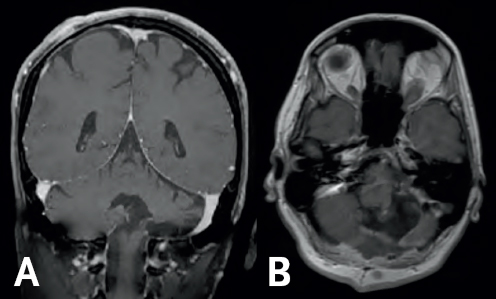

(Left) Gray colored variations are surrounded by a black and white outline. In the bottom right of the figure, there is a white blob highlighted by a yellow arrow. This blob is at the top base of a vertical dark gray column at the bottom of the image. (Right) Two dark gray spheres are conjoined at the bottom of the image. A white blob sits above the right sphere with a yellow arrow pointing towards the blob. Above the spheres are gray colored structures. All structures are enclosed by a white boarder.

FIGURE 6.1 MRI of a Glioblastoma Multiforme. Pre-operative coronal (A) and sagittal (B) MRI demonstrates a mass with central cystic areas (yellow arrows) in the left cerebellar hemisphere.

The MRI ordered by her physician demonstrated an enhancing lesion involving the intermediate zone of the left cerebellar hemisphere—suspicious for a type of malignant tumor of the brain known as a glioblastoma multiforme (GBM) (Figure 6.1).